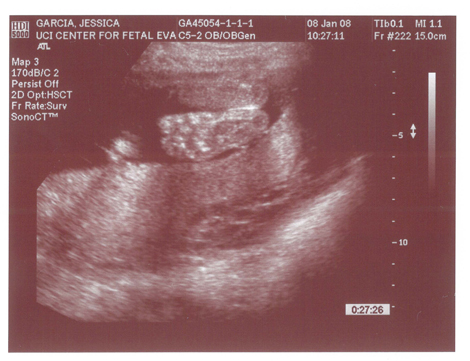

Yes we got a new dsmer coming into the world soon. We got our ultrasound today and its gonna be a boy. And shes a lot further along then we had originally thought. Shes due on April 15th which puts her at almost 6.5 months, (and really not showing it.) He weighs currently ~2lbs. He even opened his mouth while on camera which was really cool.

Here are the pics.

Pic 1: The babies head profile